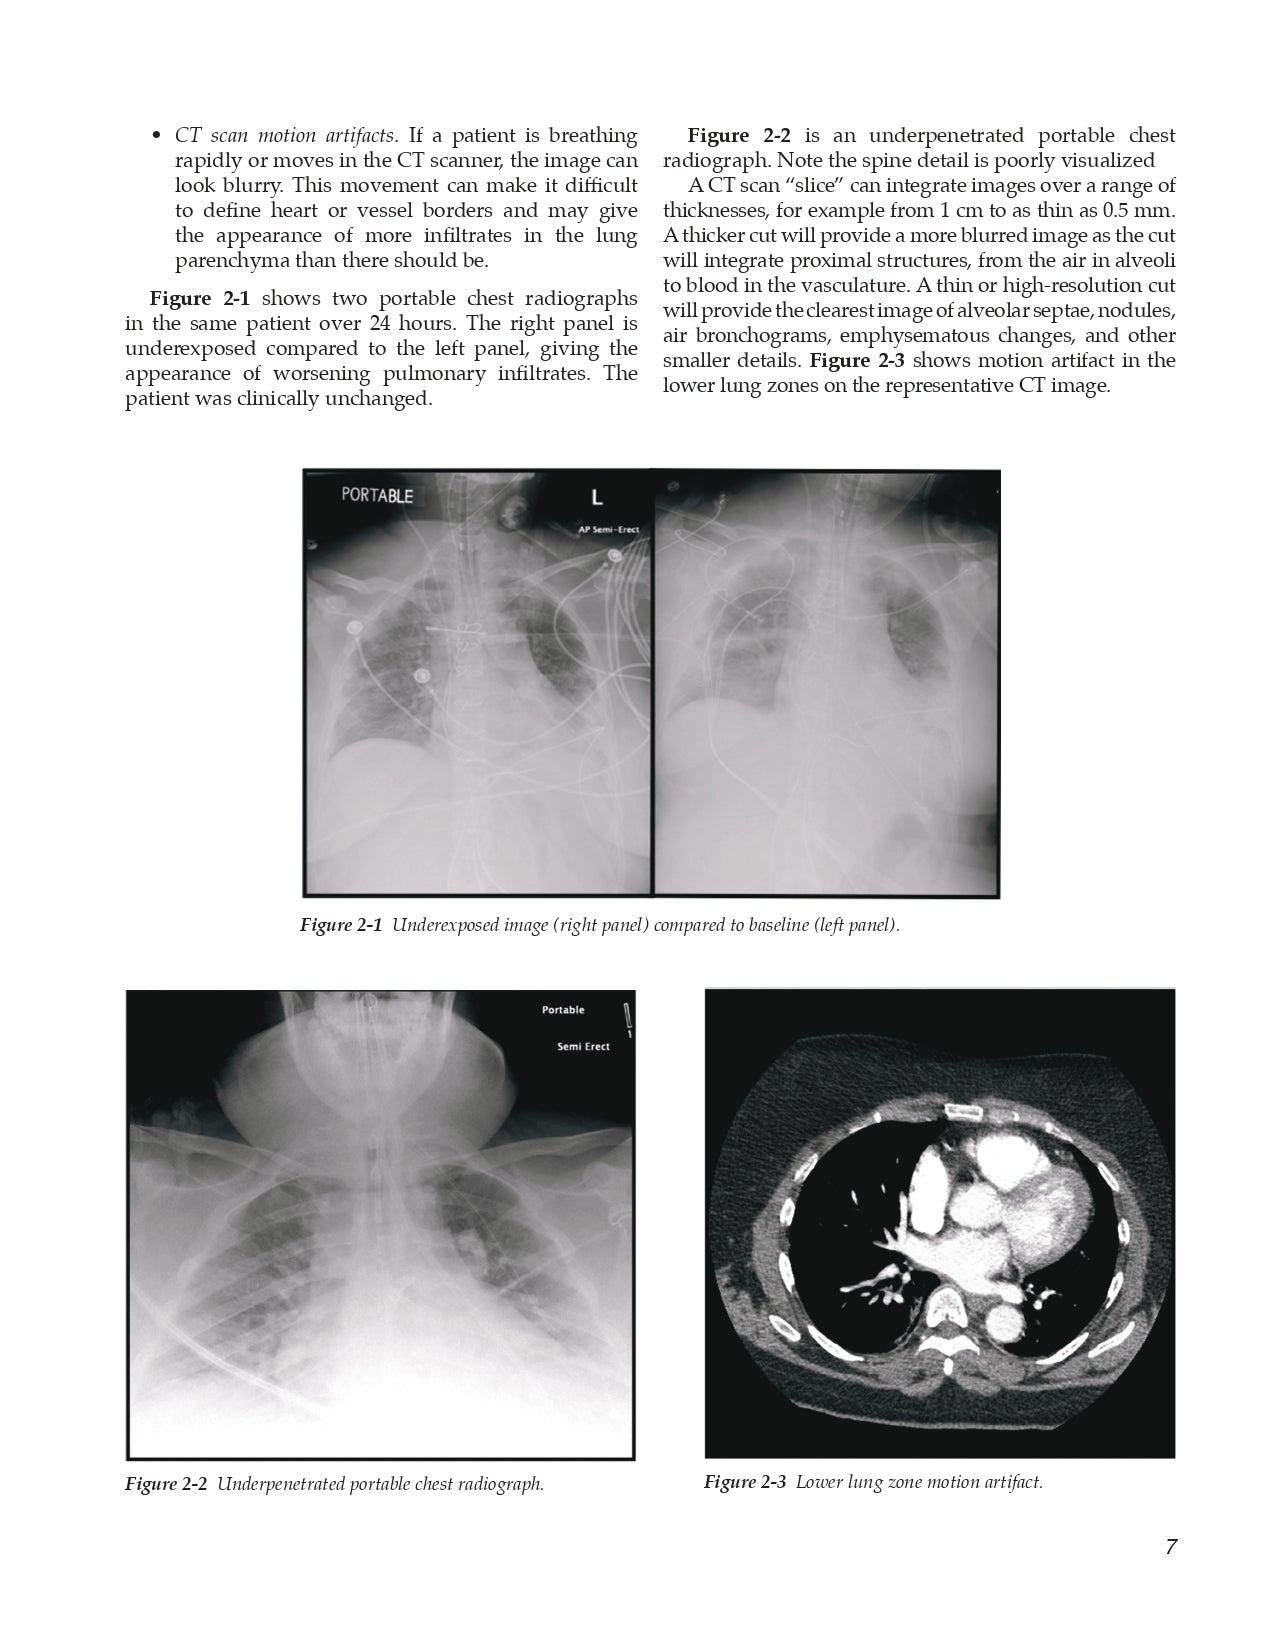

2.1 Basics of Reading Portable Chest Radiographs

- Is the Radiograph Worth Reading?